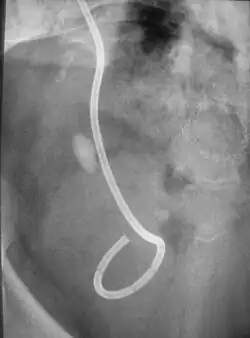

Bei der extrakorporalen Stoßwellenlithotripsie wird der Stein mit gebündelten Schallwellen so weit zerkleinert, dass die Reste auf natürlichem Wege abgehen können.[1]

Während die ersten Geräte (siehe Bild HM 1) noch eine mit Wasser gefüllte Wanne hatten, in der der Patient lag, ähneln die neueren Geräte nun einem modernen Röntgengerät mit nur noch einer Liege. Der Patient liegt auf einem beweglichen Tisch und wird an den Koppelbalg oder dieser an den Patienten herangefahren. Der Koppelbalg besteht aus einer wassergefüllten Silikonhülle, darunter liegt der Stoßwellengenerator. Diese Einheit wird leicht an den Körper des Patienten gepresst, um einen guten Kontakt zum Körper herzustellen. Zusätzlich wird ein wasserhaltiges Gel zwischen die Oberfläche des Koppelbalges und der Haut gebracht, um einen problemlosen Übertritt der Stoßwelle zu gewährleisten. Während der Behandlung erfasst das Gerät automatisch die Lage des Steines und korrigiert die Position des Patienten, falls sich der Stein während der Stoßwellenbehandlung in der Niere leicht verschiebt. Somit ist sichergestellt, dass sich der Stein immer im Stoßwellenzentrum befindet und umgebendes Gewebe geschont wird.

Außerdem kommen bei neueren Geräten neben Röntgenkameras auch Ultraschallgeräte zur Steineinstellung zum Einsatz. Etablierte Methoden zur Stoßwellenerzeugung sind elektrohydraulische (Funkenstrecke), elektromagnetische und piezoelektrische Generatoren.[4] Heute werden weltweit mehr als 3000 Geräte (Lithotripter) eingesetzt, etwa 90 % aller Nierensteine werden in den Industrieländern auf diese Art zertrümmert. 2008 gab es in Deutschland 21.892 ESWL-Behandlungen.